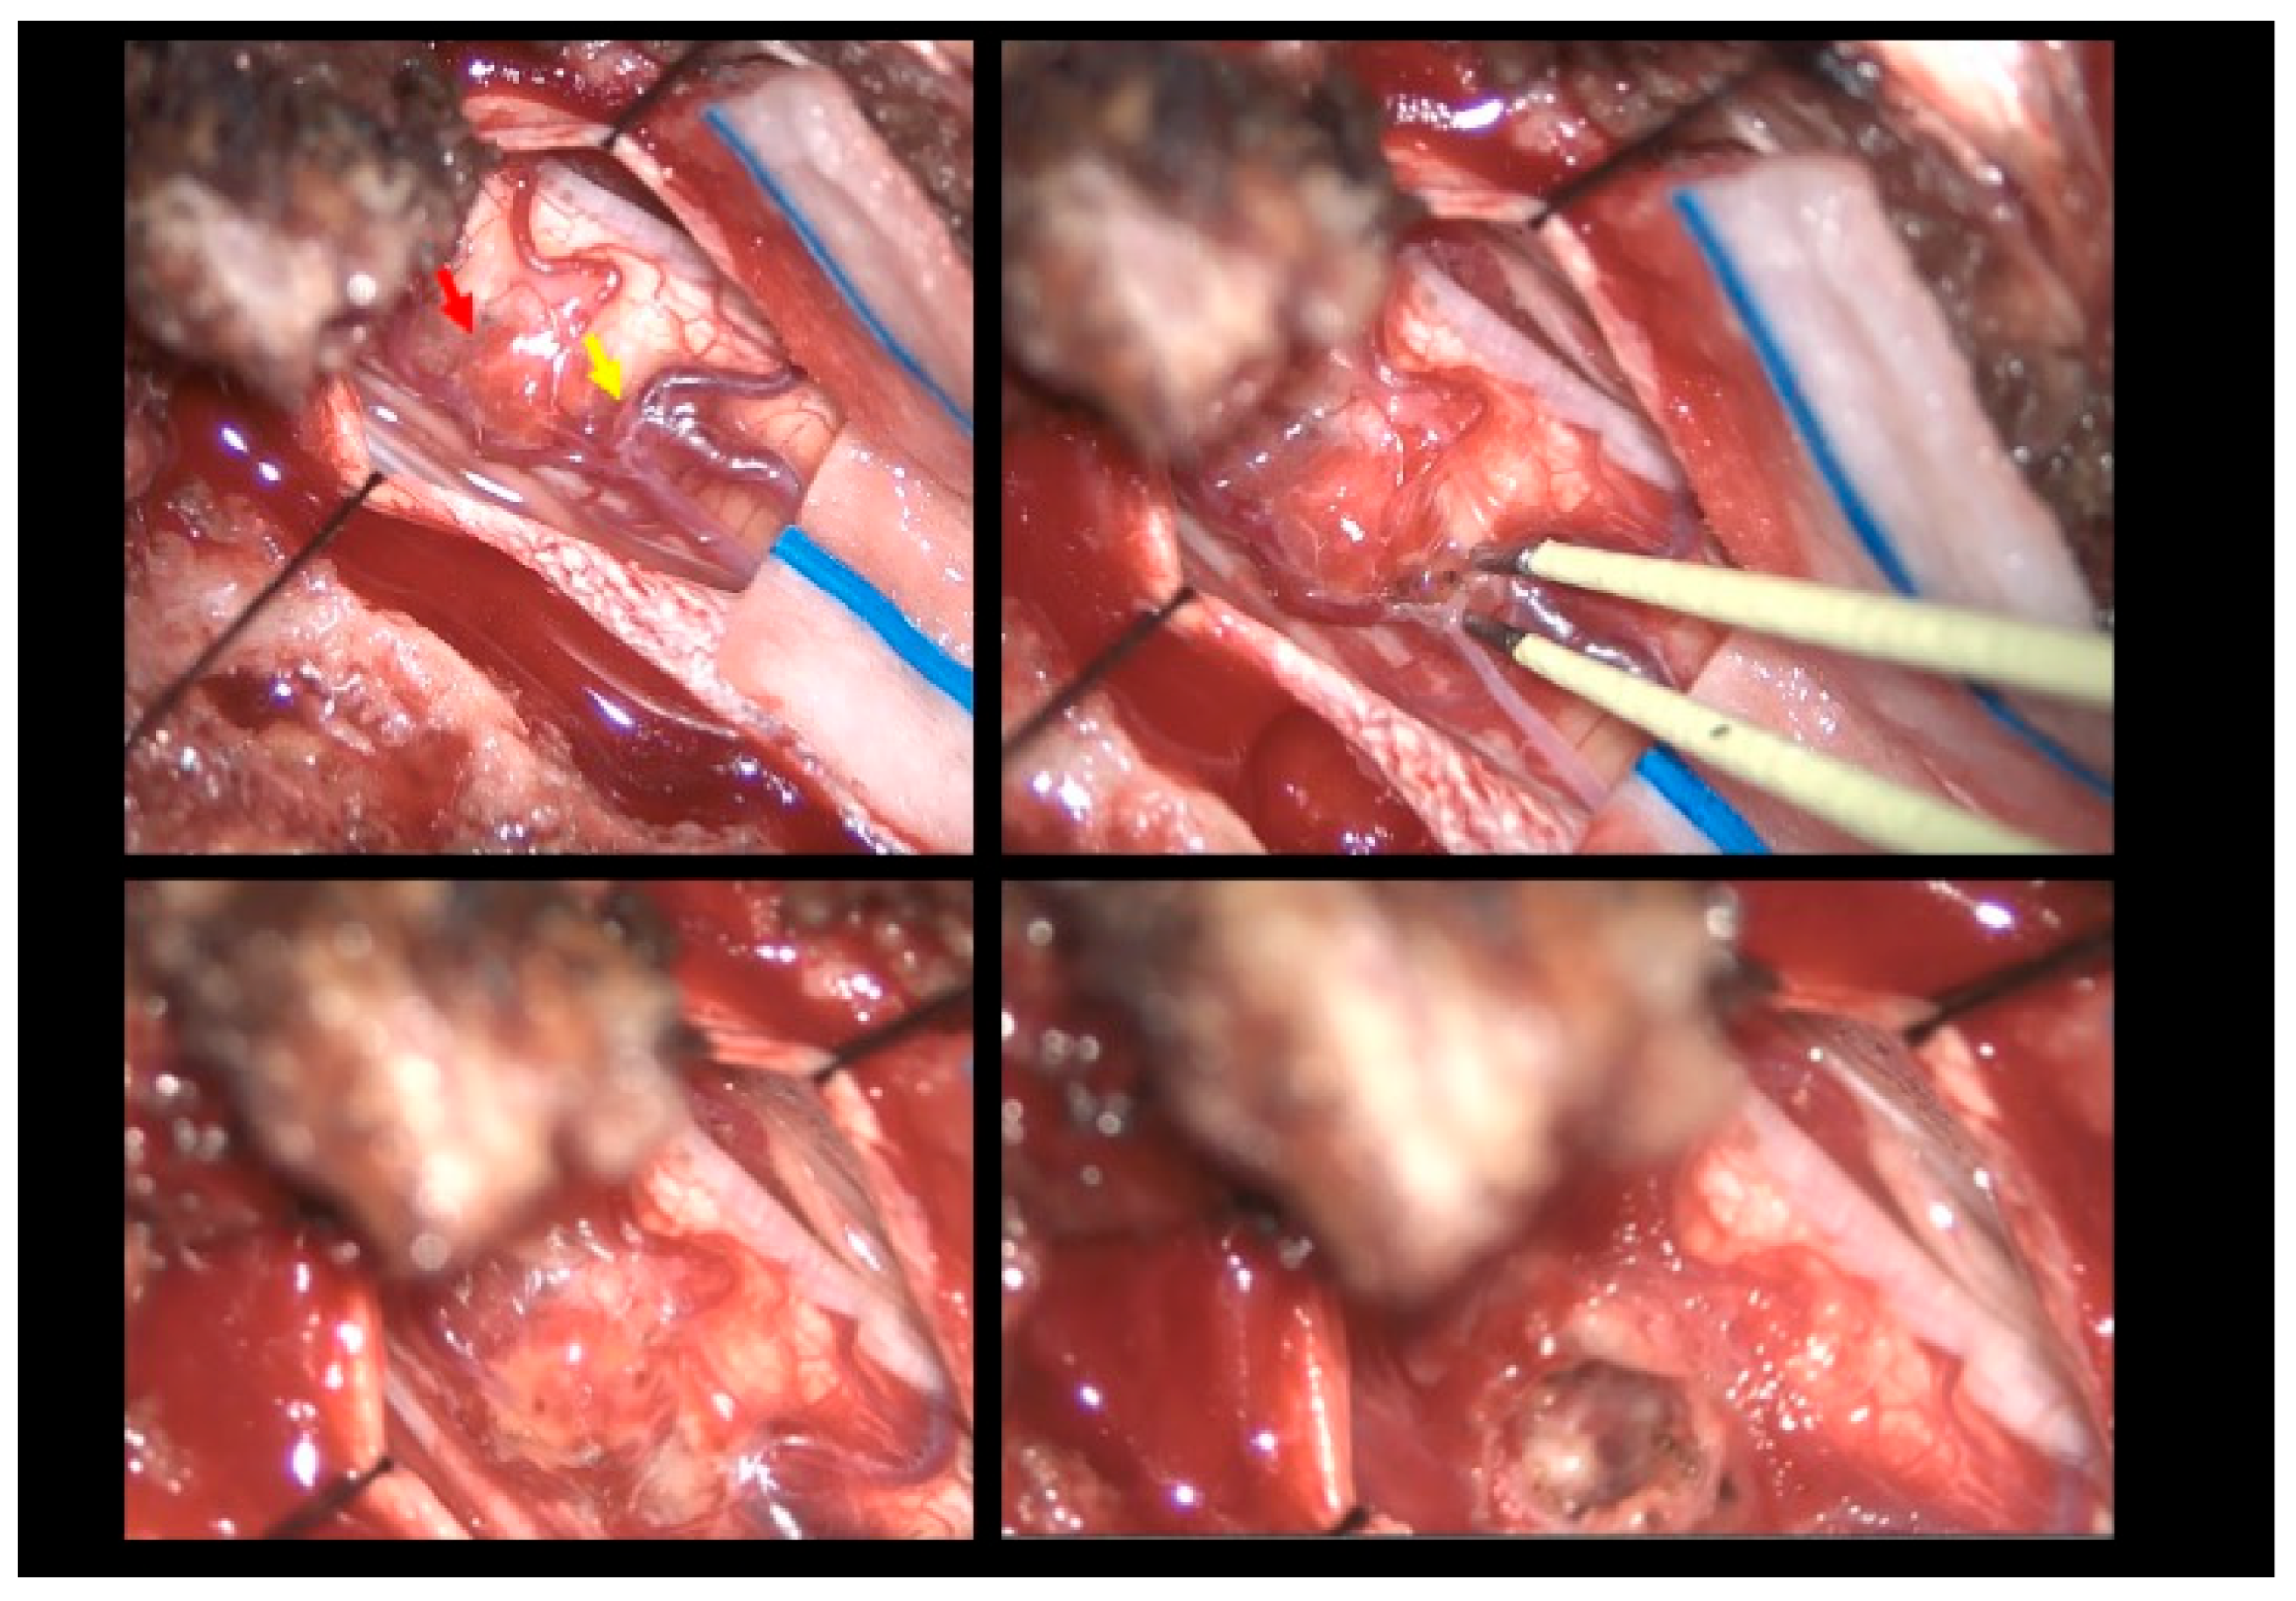

The patient was positioned prone, and a midline incision was performed, followed by bilateral muscle dissection and laminoplasty at T11–T12 using a piezoelectric osteotome (Mectron s.p.a—Carasco, Italy) [Figure 2]. Under the operating microscope, a dural opening was made, exposing the lesion, which appeared as an exophytic protrusion from the surface of the left posterior spinal cord, surrounded by a vascular malformation resembling a dural arteriovenous fistula (SDAVF) with multiple arteriovenous malformations on the pial surface [Figure 3]. Coagulation and disconnection of the fistulas were performed first by using bipolar cautery and scissor separation [Figure 3]; a detailed image of the hemangioma and the associated fistula is shown [Figure 4]. An incision was made around the lesion, which exhibited firm consistency. Due to the inability to remove the pathological tissue without traction, an ultrasonic aspirator was used for the microsurgical resection. Meticulous hemostasis was achieved. The dura mater was sutured, and a laminoplasty was performed using plates and screws. Standard wound closure was performed.

Figure 3.

Intraoperative findings. Upper left: Visualization of the hemangioma (red arrow) associated with the vascular malformation resembling a dural arteriovenous fistula (yellow arrow). Upper right: Sealing of the fistula using bipolar cautery. Bottom left: Macroscopic color change following fistula closure. Bottom right: Macroscopic appearance following hemangioma removal.

Figure 4.

Intraoperative findings. The hemangioma (red arrow) and arteriovenous fistula (yellow arrow).